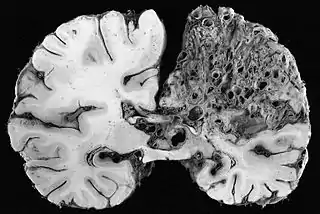

La malformación arteriovenosa cerebral o MAV es una patología vascular congénita. Se trata de arterias anormalmente dilatadas que desembocan directamente en venas también anómalas (arterializadas), sin la interposición normal de una red capilar entre ellas,[1] sustituyéndose al capilar por un ovillo enmarañado de vasos sanguíneos irreconocibles; por lo que el paso de sangre desde la arteria a la vena se hace de una manera muy veloz, haciendo que la vena se dilate y corra el riesgo de romperse. Tienen el aspecto de una masa retorcida de tamaño anormal y un color grisáceo. Son lesiones muy poco comunes, ya que ocurren en menos del 1% de la población (3 de cada 10000 personas). Se presenta más comúnmente entre los 15 y 20 años, aunque también puede manifestarse posteriormente.[2]

![]() Vista macroscópica de malformación arteriovenosa en el lóbulo parietal. | ||